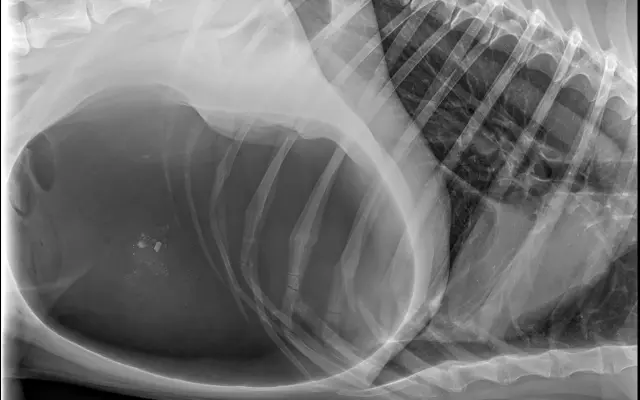

Fotogalerie